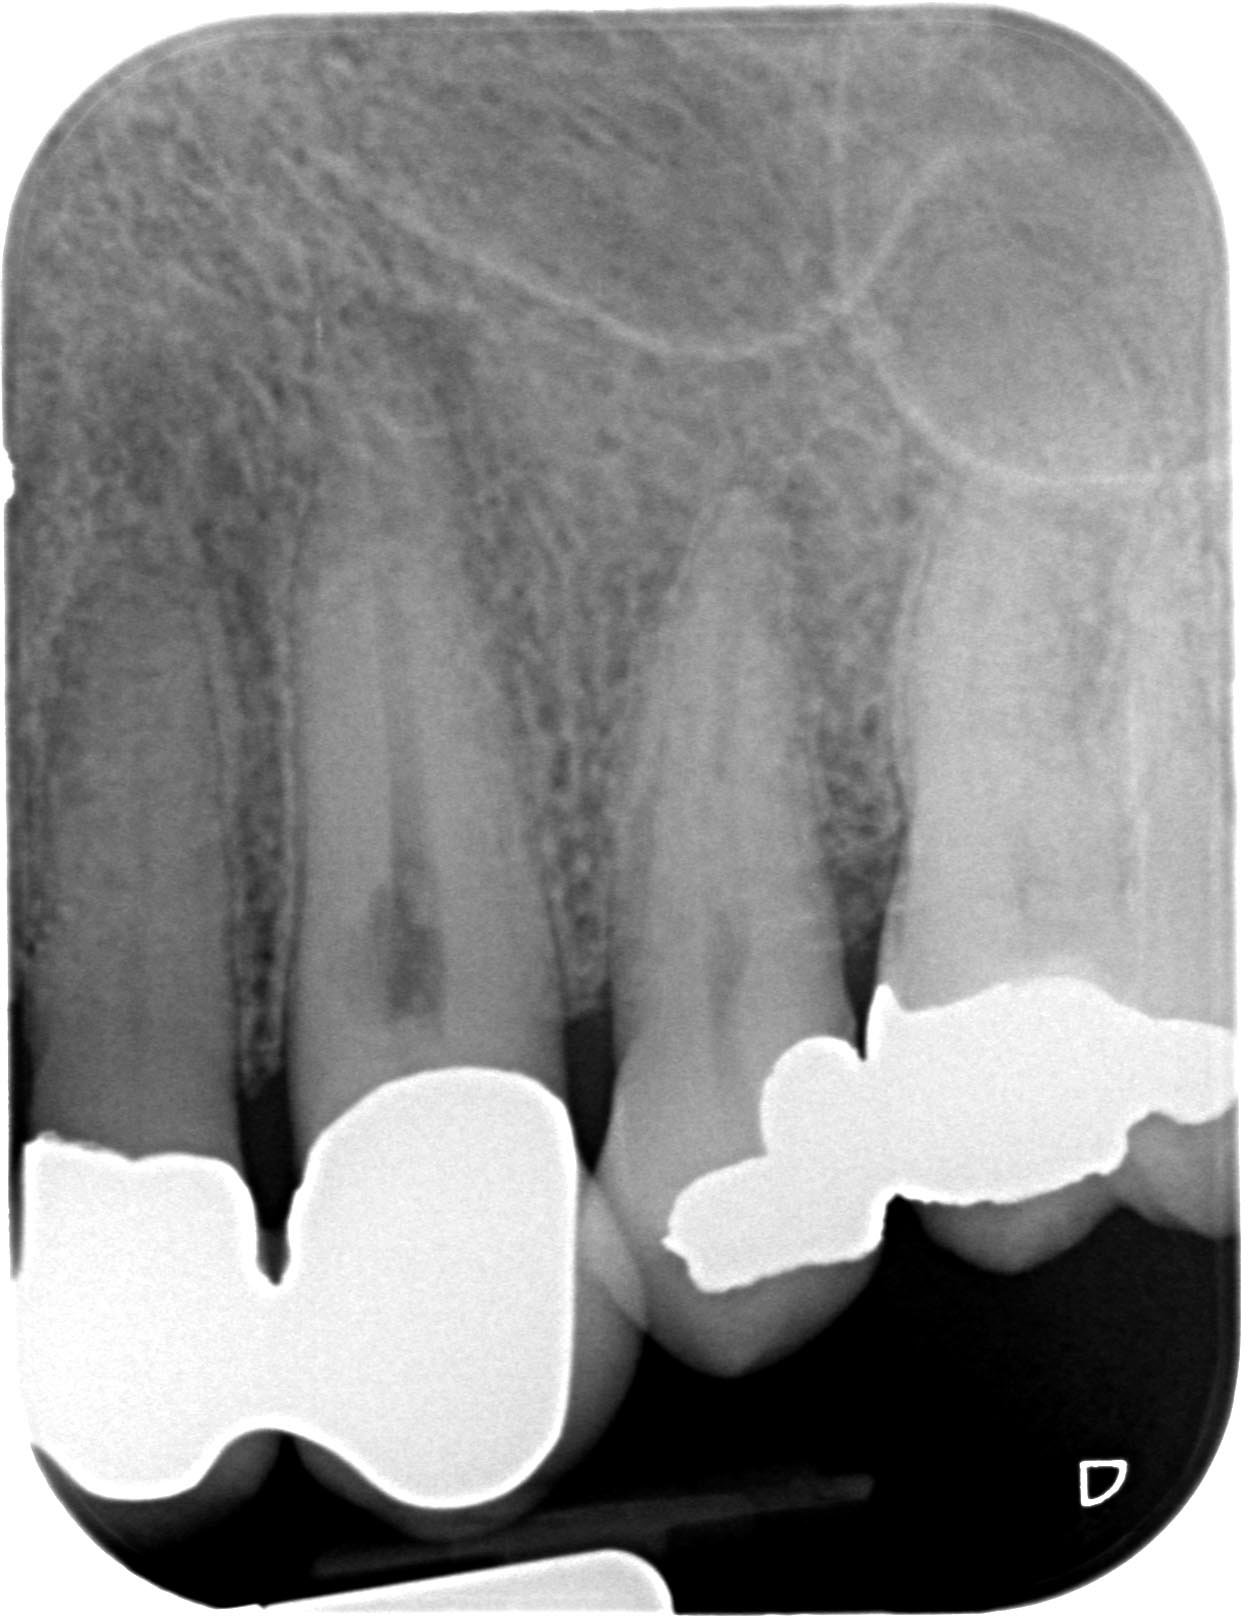

Resorption-2-2 Veröffentlicht 10. Juni 2013 am 1252 × 1621 in Was zeigt das DVT (4) ? Die Fälle Zahn 12, 13, 14, 15